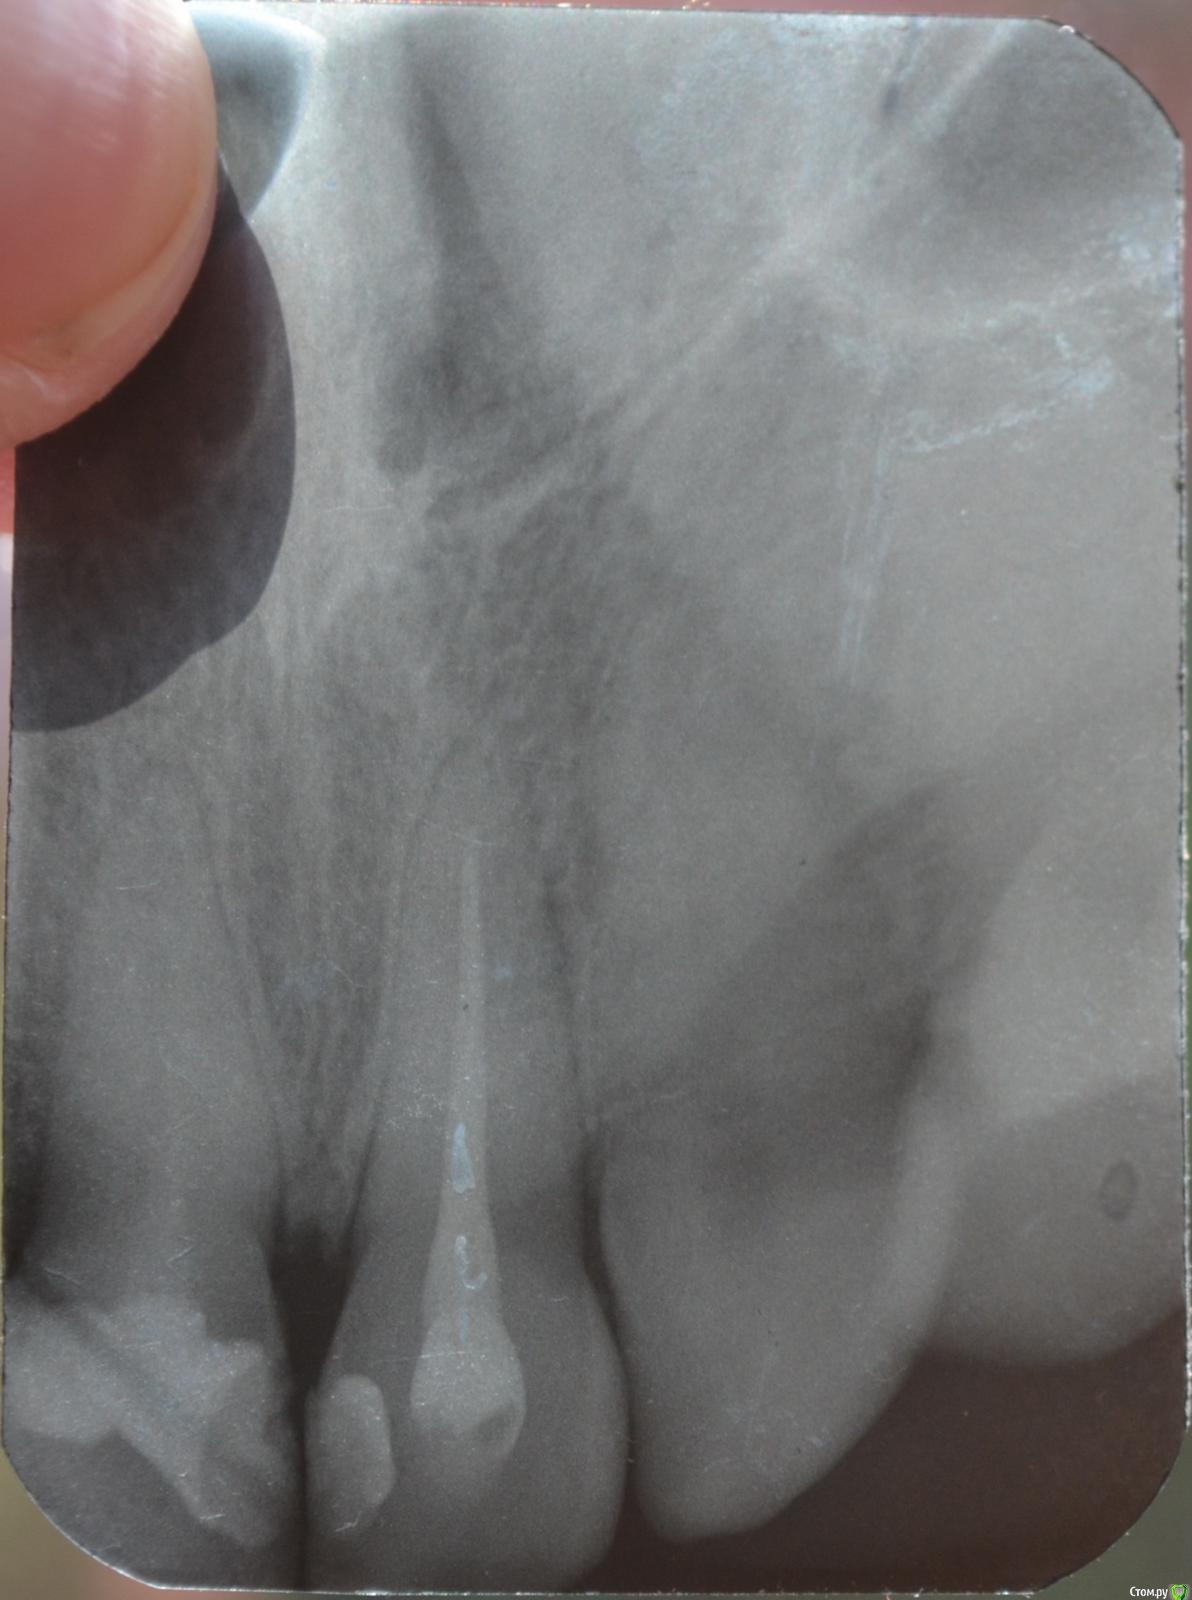

Llllll Опубликовано 11 июля, 2015 Автор Поделиться Опубликовано 11 июля, 2015 1 справа верхний, до того как открыли недавно каналы. Ссылка на комментарий

shishok Опубликовано 12 июля, 2015 Поделиться Опубликовано 12 июля, 2015 Лучше бы прицельный снимок проблемного зуба(на ОПТГ ничего не видно). Ссылка на комментарий

Llllll Опубликовано 12 июля, 2015 Автор Поделиться Опубликовано 12 июля, 2015 Лучше бы прицельный снимок проблемного зуба(на ОПТГ ничего не видно).Это 2 снимка этого зуба, несколько раз сфотографировала, чтоб лучше было видно. Ссылка на комментарий

Llllll Опубликовано 12 июля, 2015 Автор Поделиться Опубликовано 12 июля, 2015 И есть ли воспаление корня на снимке? (правого или левого). Вообще врач думал во вторник удалять передний зуб, который болит. К другому врачу не могу пойти, так как город маленький, и врачей всего несколько. Это уже третий врач у которого была, и никто не знает что с зубом делать, и вообще от него ли это( Ссылка на комментарий